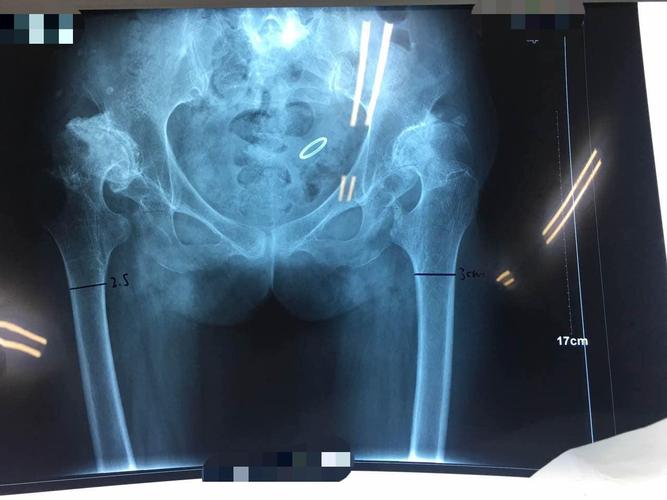

双侧髋关节置换后能和正常人一样么

双侧髋关节置换后能和正常人一样么?女性在怀孕期间身体会经历变化,包括生理性的变化,病理性的变化,以及病理变化等,都会导致双侧髋关节置换后无法正常生育。那么双侧髋关节置换后可以和正常人一样吗?

首先,双侧髋关节置换后正常人也是有这种病理性的,只不过是病理性的,可以在身体情况允许下考虑生育,如果在此期间没有发生怀孕,可以考虑在怀孕三个月左右做相关的检查,观察身体变化是否正常,如果没有异常,一般都是可以考虑的。

其次,双侧髋关节置换手术后,应避免长期负重,可适当散步,做低盘运动,锻炼腿部肌肉的活动幅度较大,适当锻炼饭后性生活,避免吃辛辣刺激食物,保持心情愉快。另外,孕妇在孕期也要多补钙,多晒太阳,不能自己“滥吃”补钙,以免影响胎儿正常发育。